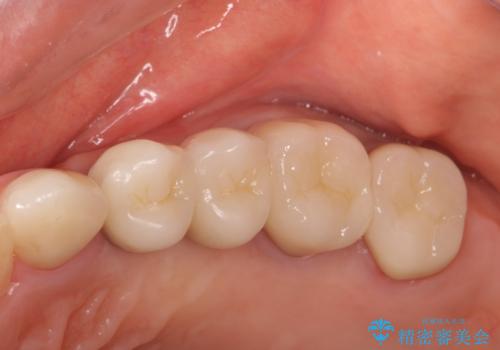

銀歯を除去したのち、虫歯を丁寧に除去し、歯を残せるのかどうかをしっかりと評価し、長期的な予後を見据えた虫歯治療を行っていきます。

- 154万円(インプラント×2・チタンカスタムアバットメント×2・ジルコニアクラウン×6・仮歯×6)費用は治療当時の料金となります

銀歯の下で虫歯が再発していた歯は、無理に残しても割れてしまう可能性が非常に高いと考えたため、相談の上抜去を行いインプラント治療を行っていくこととしました。